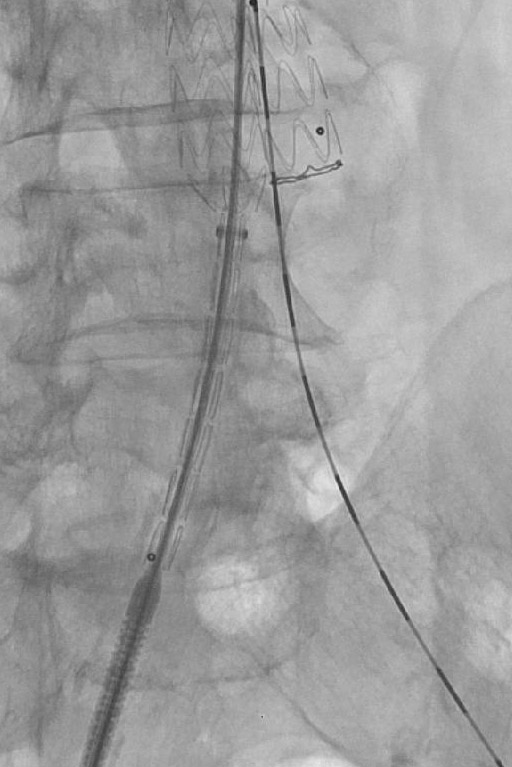

Symedrix has developed the WiTRAC® pre-shaped and scaled guide wire specifically designed to improve AAA procedures.

The AAA wire has three independent zones of stiffness providing optimal support. The ultra-stiff proximal portion of the wire facilitates easy advancing of introducer sheath. The super-stiff distal portion adapts perfectly to the anatomy in the abdominal aortic area and provides sufficient guidance and support for the AAA introducer system. The scaling provides additional support during endovascular procedures. The Tip allows atraumatic positioning in Aorta, thereby protecting the Vessels during the implantation of the stent grafts.

The stiff core wire provides excellent guidance for all AAA devices. It is engineered to enhance torque transmission and support precise positioning.

A PTFE-coated, stainless steel wire is the key to providing maximum support and low surface friction during complex procedures.